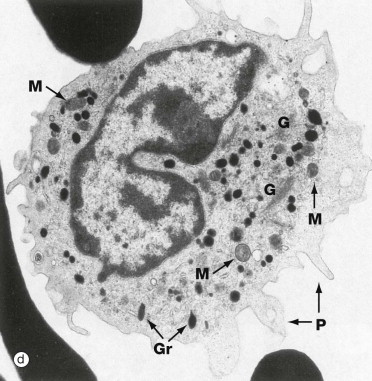

What is this cell?

Monocyte